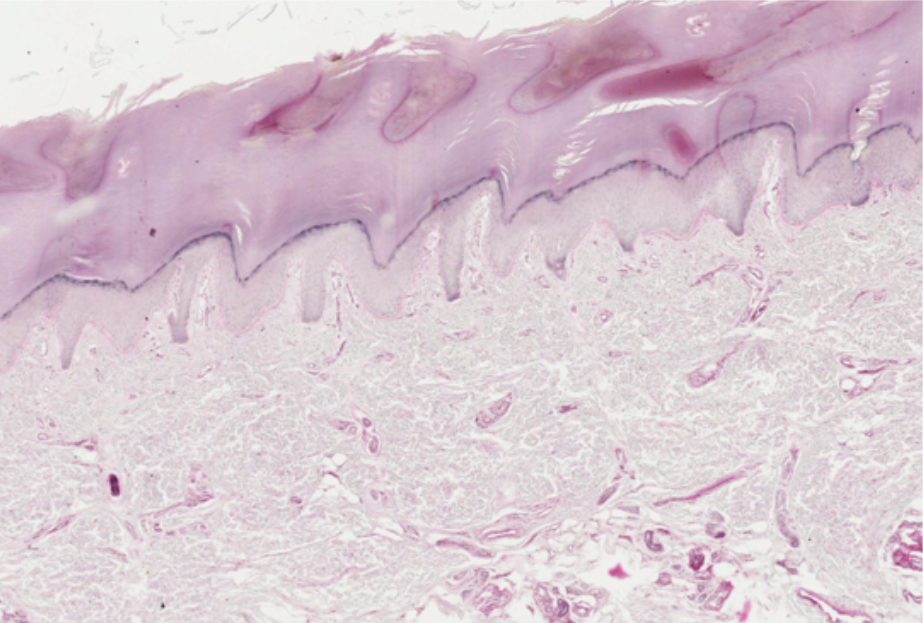

thick skin

thin skin